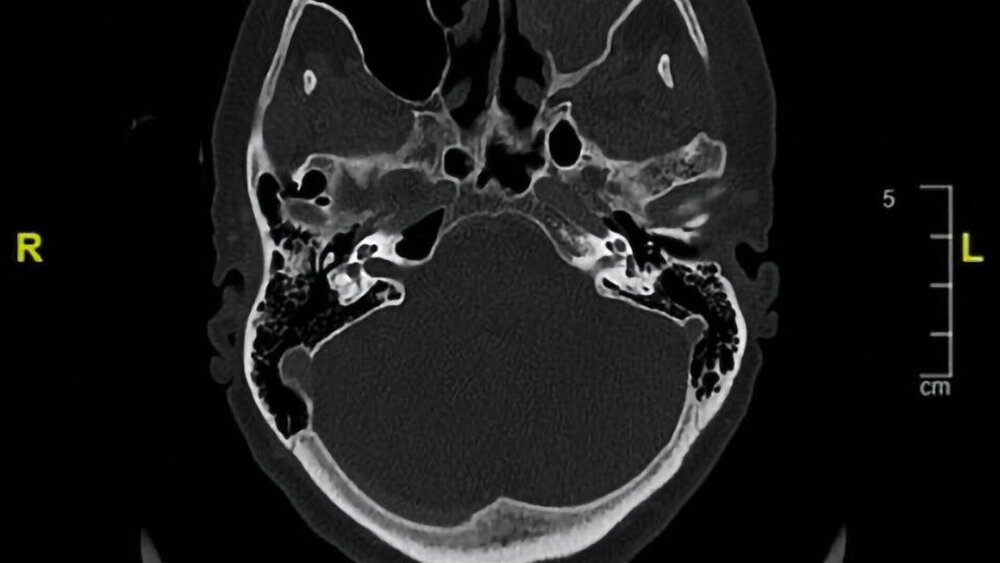

Klinisch imponierte eine deutliche Schwellung am linken Unterlid ohne Visus- und Sensibilitätsstörungen. Im Rahmen der intraoralen Inspektion zeigte sich ein verstrichenes Vestibulum an der Crista zygomaticoalveolaris links mit deutlichem Palpationsschmerz über der fazialen Kieferhöhlenwand. Die computertomografische Untersuchung zeigte eine vollständige Verlegung des linken Sinus maxillaris mit knöchernen Arrosionen der Kieferhöhlenvorderwand, medialen Kieferhöhlenwand, der Ethmoidalzellen und Infiltration des Orbitabodens sowie Einbruch in das Subkutangewebe der Wange (Abbildung 1).